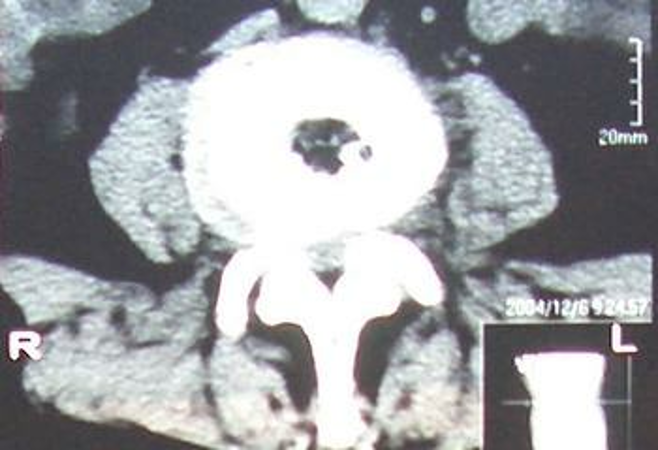

2、经皮腰椎间盘切吸术(PLD)在影像监控下,将工作套管直接进入椎间盘内,利用钳夹切割及负压系统取出部分髓核,从而降低盘内压力,使纤维环压力减轻,解除对神经根的压迫。

Thessys椎间孔镜优缺点THESSYS可以用于任何疝出的椎间盘微创伤手术。所有隔离的椎间盘物质和腰部脊柱的脱出(包括第5腰椎和第1骶椎间隙)都可以使用整个系统在局麻下经侧方的椎间孔摘除。整个系统的使用适用于任何由疝出的椎间盘或较大的突出引起的神经根症状或长期疼痛,保守治疗不能获得足够的改善。对于任何疝出的椎间盘的手术,THESSYS手术也需要术前彻底的磁共振,计算机断层和常规的放射线影像检查。